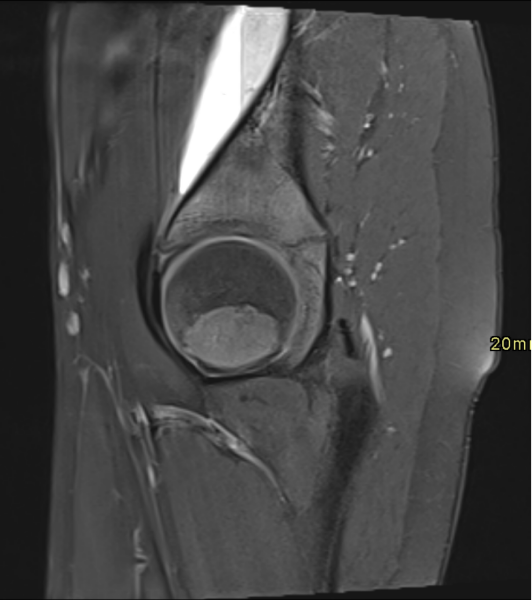

RM de cadera izquierda, secuencia PD TSE FS axial (Imagen 1) y sagital (Imagen 2). Se observa una imagen lentiforme subperióstica ilíaca de alta señal, bien delimitada, con un nivel líquido-líquido.